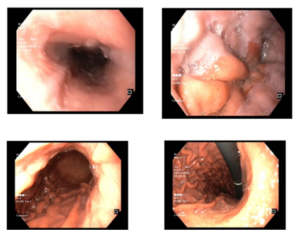

Ca lâm sàng: Điều trị bệnh nhân ung thư phổi di căn màng phổi, màng tim tại Trung tâm Y học hạt nhân và Ung bướu, Bệnh viện Bạch Mai

Ca lâm sàng: Điều trị bệnh nhân ung thư phổi di căn màng phổi, màng tim tại Trung tâm Y học hạt nhân và Ung bướu, Bệnh viện Bạch Mai GS.TS. Mai Trọng Khoa, PGS.TS.Phạm Cẩm Phương, BS CKII Võ Thị Huyền Trang, BS. Vũ Thị Huyền Ung thư phổi...